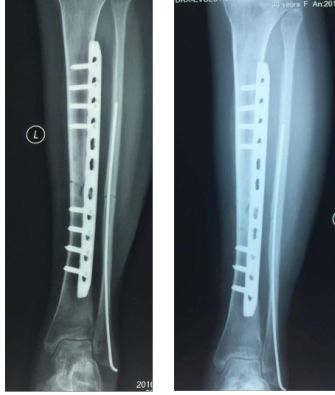

此处用钢板失败率极高,取出内固定后应力集中,(外侧孔或坚强固定内固定的应力遮挡影响局部的骨质、钢板下皮质骨吸收。)都是断裂原因,此病人明显有孔。

点评:可能的原因手术不当,剥离过多而没有植骨;钢丝多此一举;康复不利关节僵硬。骨质疏松提示功能不好。取出钢板骨断裂,取出后片子显示骨折愈合不良;因为功能差桡骨头切除

教训:新鲜孟氏骨折尺骨复位桡骨头即可复位,必要时修复外侧韧带。早期功能锻炼很重要。近关节的骨折愈合不好关节僵硬取出内固定后更容易断裂;不熟悉的方法要有人指导或不用。钢丝代替环韧带有适应症,不适合新鲜骨折。